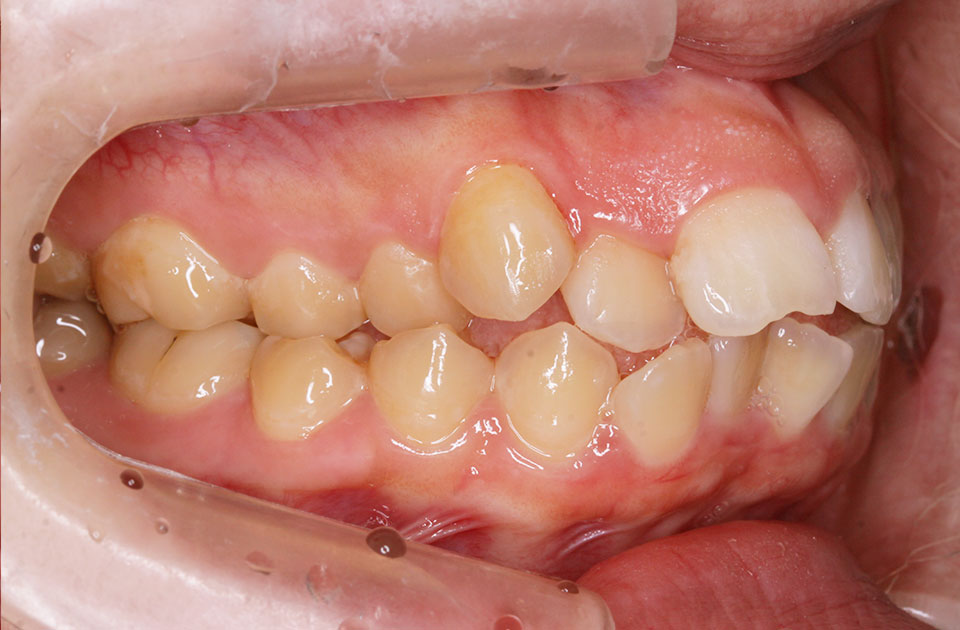

矯正前 右側

矯正前 左側